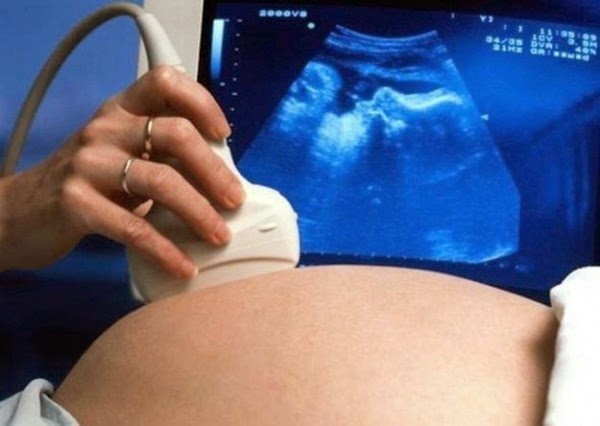

Se puede evitar realizando un ciclo de Fecundación in Vitro y Diagnóstico Genético Preimplantacional (DGP). Esta técnica se realiza en el embrión antes de su implantación en el útero. El DGP informa sobre el estado de cada uno de los embriones concebidos, y permite que únicamente los sanos sean transferidos al útero.

La gran mayoría de los embriones con anomalías cromosómicas no concluyen con embarazo o bien acaban en abortos. Los embriones que evolucionan pueden resultar en el nacimiento de un niño afectado de alguna patología.